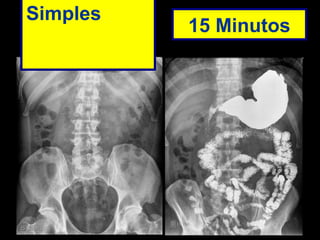

Abaixo exame de transito intestinal de um paciente do sexo masculino, 50 anos, com quadro de diarréia. No exame realizado observaremos o trânsito intestinal acelerado.

Simples  15 Minutos

Abaixo exame detransito intestinal de um paciente do sexo masculino, 50 anos, com quadro de diarréia. No exame realizado observaremos o trânsito intestinal acelerado.

Simples 15Minutos